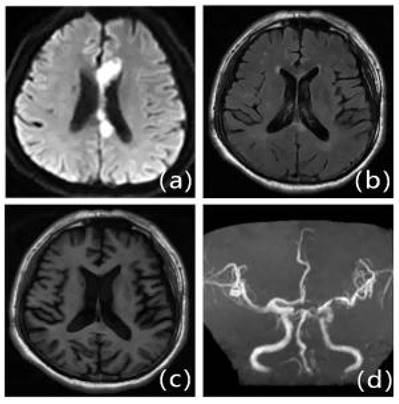

Figure 2

MRI presentation of LA. a: FLAIR, b: T1WI, c: T2WI, d: DWI.

We retrospectively studied patients with first IS (≥18 years of age, onset <72 hours) admitted to the Second Department of Neurology at the Affiliated Hospital of Weifang Medical College from January 2018 to January 2023. Out of 1701 patients, 504 patients who met the criteria eventually became the final sample to be included in this study (Figure 1). Patients underwent diffusion-weighted magnetic resonance imaging (DWI), magnetic resonance angiography (MRA), computed tomography angiography (CTA), and/or digital subtraction angiography (DSA). The DWI/Apparent Diffusion Coefficient (ADC) lesions of all patients were matched with their clinical stroke manifestations. Clinical data were collected, including demographic data (sex, age, admission National Institutes of Health Stroke Scale (NIHSS), and time of admission) and risk factors (hypertension [7], diabetes [8], coronary artery disease [9], dyslipidemia, smoking history, and drinking History), as defined in previous reports [10]. The determination of ICAS was based on ancillary examinations such as cranial magnetic resonance angiography (MRA), computerized tomography angiography (CTA) or digital subtraction angiography (DSA), and the stenosis rate = (1 - stenosis diameter/normal diameter). DSA and other ancillary tests were calculated using the method described in the Warfarin, Aspirin for Symptomatic Intracranial Disease (WASID) study, with stenosis rate = (1 - stenosis diameter/normal diameter) × 100%, and inclusion in the study required that intracranial vascular stenosis was ≥50% or occlusion [2], all of which were performed by a clinician with more than 5 years of clinical experience. We also collected clinical data for the following imaging modalities: MRA, CTA, DSA or magnetic resonance imaging (MRI), carotid ultrasound, electrocardiogram or 24-hour ECG (Holter), Doppler echocardiography and right heart acoustic angiography (completed within 3 days of admission). The MRI manifestation of LA is shown in Figure 2. All patients were fasted after 20:00 on the night of admission, and the collection of specimens for the fasting blood test program was completed early the next morning. Laboratory tests included homocysteine (Hcy),high-sensitivity C-reactive protein (HsCRP), red blood cell (RBC), white blood cell (WBC), platelet count (PLT), absolute neutrophil value, absolute lymphocyte value, hemoglobin (Hb), sedimentation, prothrombin time (PT), activated partial thromboplastin time (APTT), international normalized ratio (INR), fibrinogen (FIB), D-dimer, total cholesterol (TC), triglycerides (TG), high-density lipid cholesterol (HDL-C), and low-density lipid cholesterol (LDL-C), urea, creatinine, albumin, alkaline phosphatase, uric acid (UA), glucose and glycohemoglobin A1c (HbAlc).